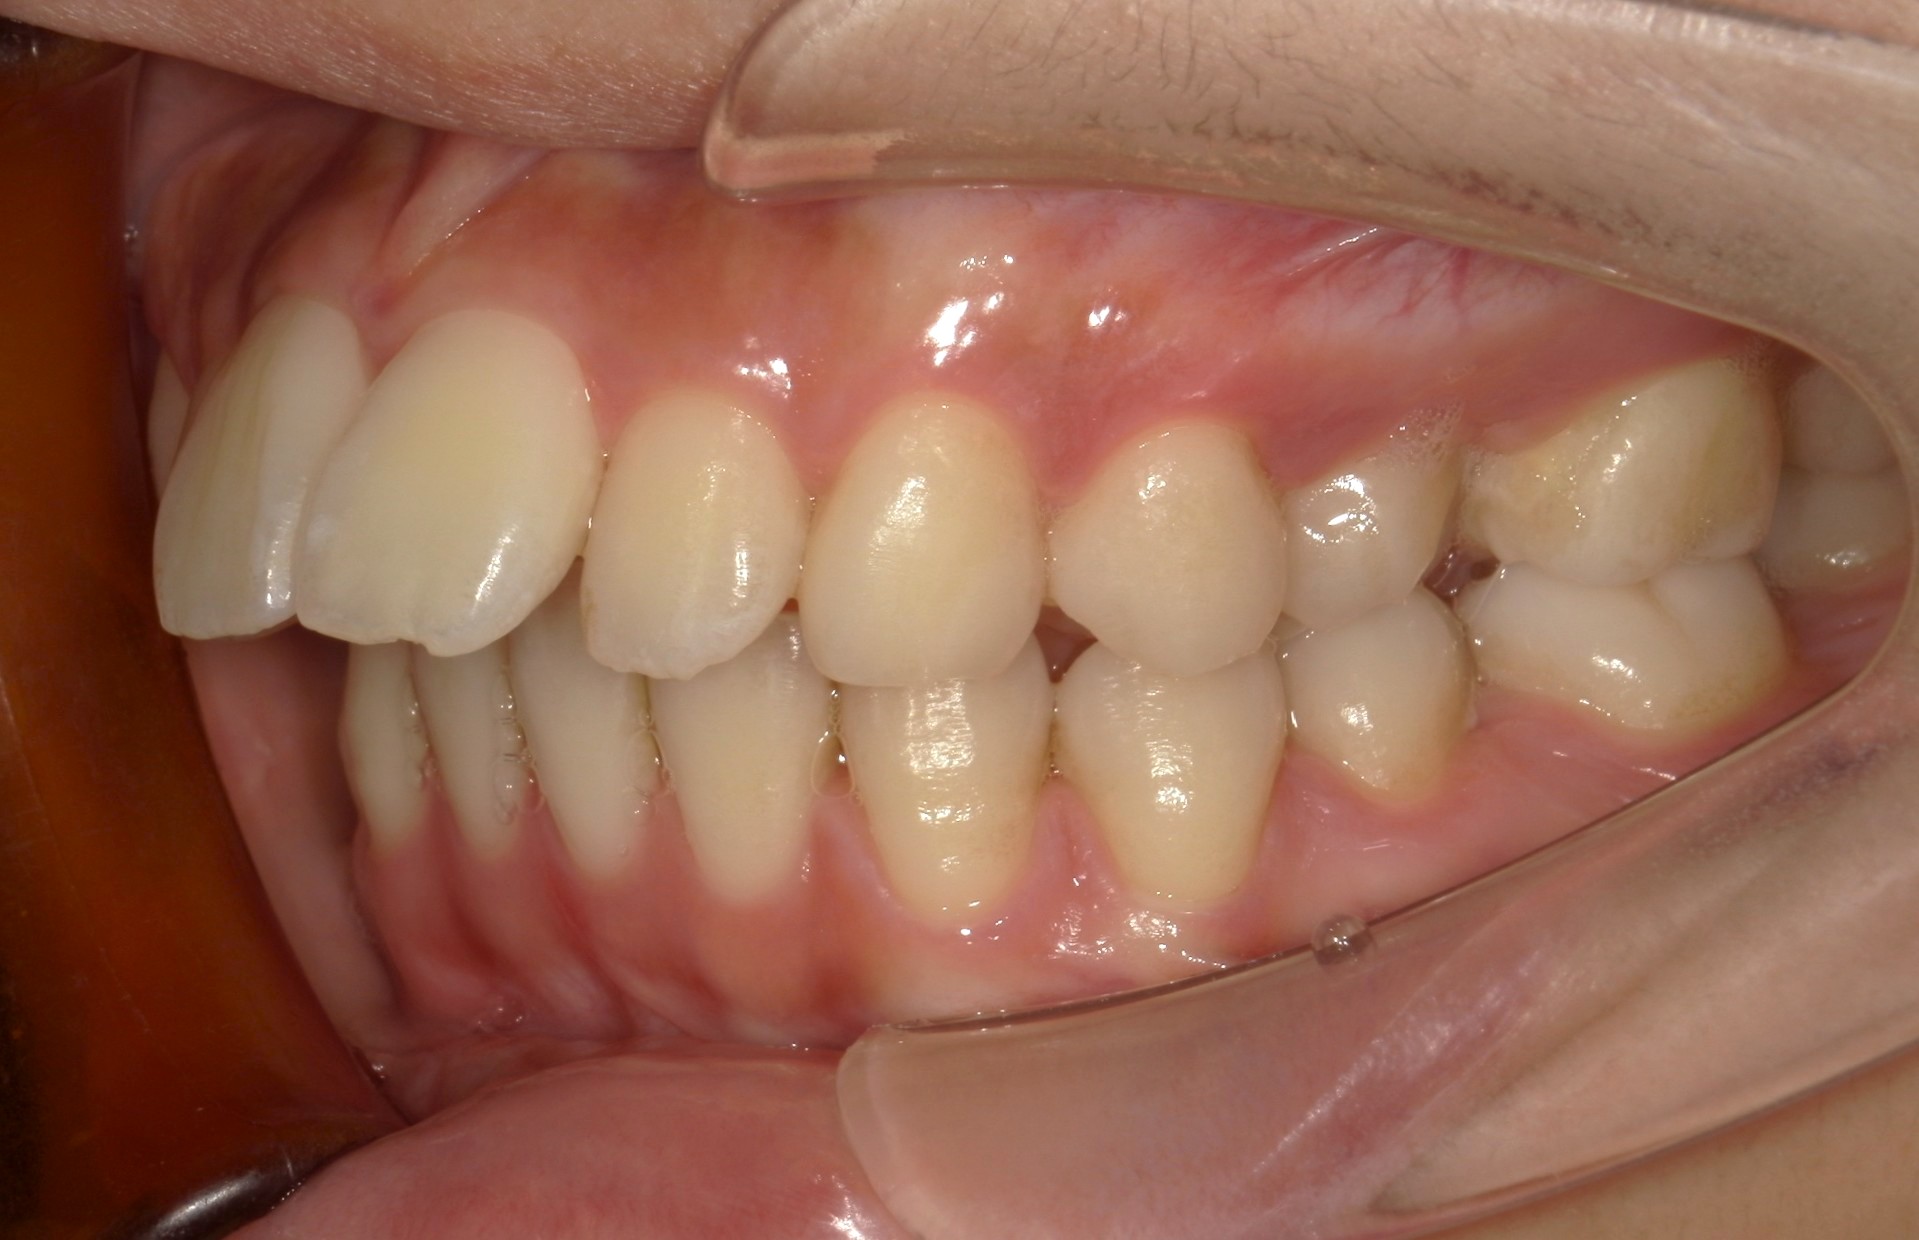

横から見た口腔内写真でよくわかるように、前歯が出っ歯になっており、全く咬んでいない状態でした。また下の前歯が本来4本あるところが、先天的に一本少なく3本しかない(Three incisors)であったため下顎のアーチが小さいというお口の状態でした。前歯を正しい傾きに治し、咬合させるため、上の歯のみ2本の抜歯を行うこととしました。下の前歯が3本のため、その正中に注意しながら前歯の傾きを修正し、奥歯のポジションを整えて仕上げました。口元の突出感は大きく改善し、咬合も良好な状態で完了することができました。

口内左

治療前

治療後